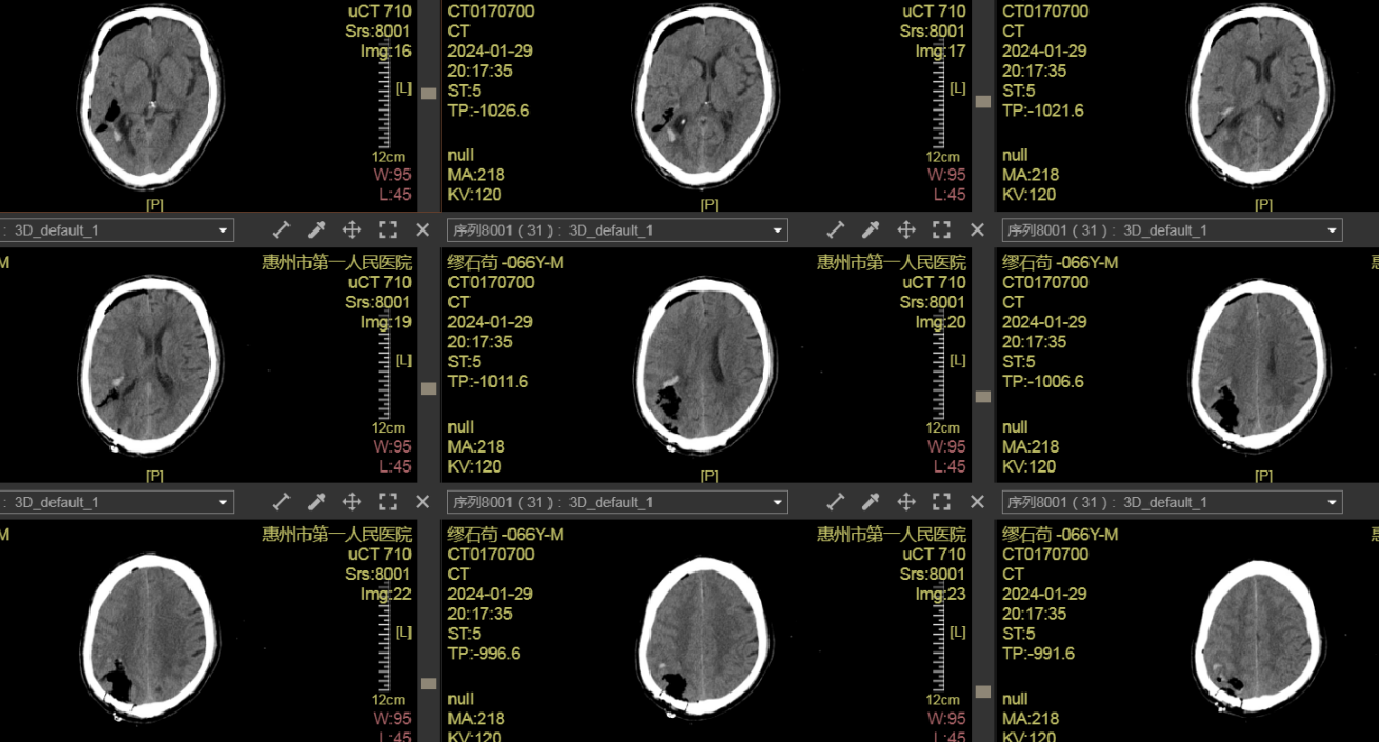

术后CT

出院情况:患者神志清楚,GCS评分15分。

左侧鼻唇沟变浅,口角向右歪斜。构音欠清晰,伸舌居中。

左侧肌力4级,右侧肌力5级。四肢躯体深浅感觉正常。

NIHSS评分:3分(面瘫1,左上肢肌力1,左下肢肌力1)。